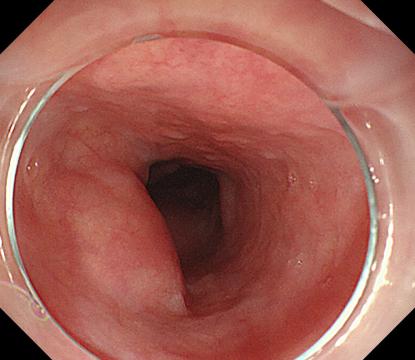

特色技術:科室在萎縮性胃炎及消化道早癌、非酒精性脂肪性肝病、胃食管反流病、慢性肝病等常見多發病以及急性上消化道大出血、重癥急性胰腺炎等急危重癥和疑難雜癥的治療方面具有鮮明特色。消化內鏡中心常規開展了無痛電子胃腸鏡檢查、超聲胃鏡檢查、膠囊內鏡檢查、胃鏡下取異物、食道支架植入術、內鏡下胃造瘺術、食管-胃底靜脈曲張破裂出血套扎術及組織膠注射、內鏡黏膜下剝離術(ESD)、內鏡下全層切除術(EFTR)、經內鏡黏膜下食道腫瘤切除術(STER)、內痔硬化及套扎微創治療等內鏡診治技術,新開展內鏡超聲引導下細針穿刺活檢(EUS-FNA)、抗反流黏膜切除術(ARMS)等新技術新項目10余項,內鏡技術實力處于渝西領先水平。